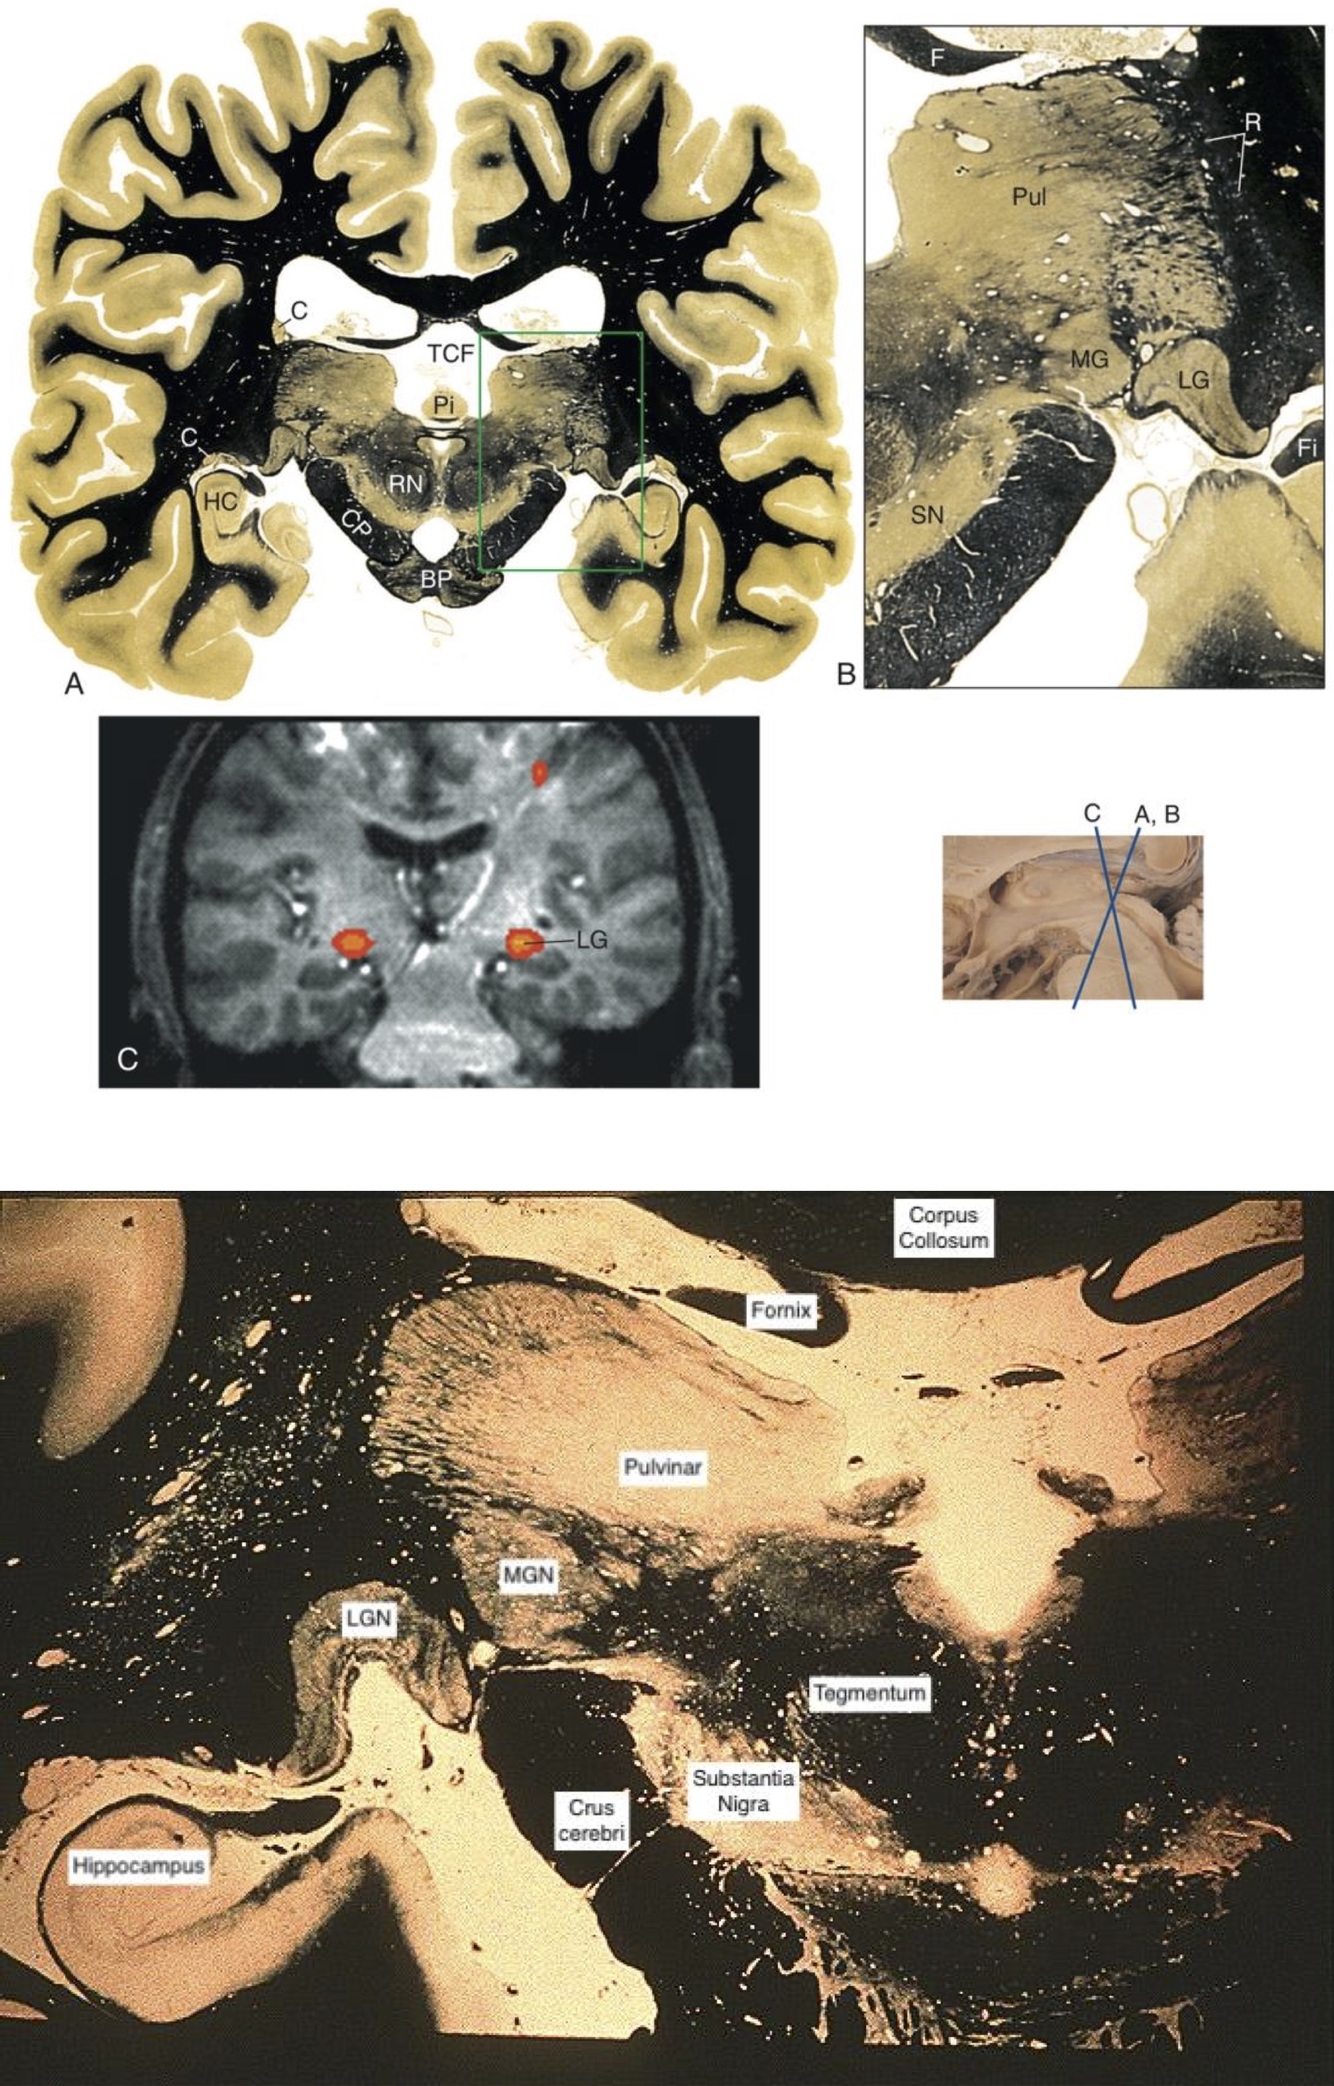

Thalamus

Caudal Most Portion